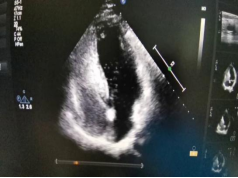

3、經(jīng)食道超聲心動圖及右心聲學(xué)造影

經(jīng)食道超聲心動圖用于精準(zhǔn)評價(jià)心臟內(nèi)血栓、卵圓孔未閉的類型及大小、心臟瓣膜損傷、感染性心內(nèi)膜炎等,也便于進(jìn)行心臟手術(shù)中的超聲監(jiān)測與評價(jià),科室近年來在經(jīng)食道超聲心動圖檢查及診斷上積累了豐富的經(jīng)驗(yàn)。

右心聲學(xué)造影可進(jìn)一步提高卵圓孔未閉、房間隔缺損、肺動靜脈瘺、永存左上腔靜脈等異常的超聲檢測率,尤其是不明原因的偏頭痛的病因篩查,科室開展右心聲學(xué)造影數(shù)百例,為偏頭痛的患者查找出了病因,為臨床治療提供了可靠的診斷依據(jù)。